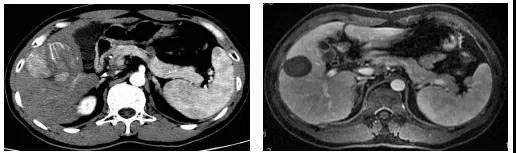

相较于西方国家,我国肝癌患者的肿瘤负荷更大,门静脉癌栓(PVTT)比例更高。此种情况下,药物洗脱微球栓塞术(DEB-TACE)可改善传统TACE在治疗>5cm肝癌的不足,微球和药物的高亲和性,可持续、缓慢释放药物而提高局部药物浓度、降低全身药物浓度,达到疗效和耐受性的改善。我们研究团队在一项利用DEB-TACE联合FOLFOX HAIC治疗大肝癌的研究中(Zhu KS,et al. J Hepatocell Carcinoma. 2021, 8;8:1445-1458.),发现该方案较单独DEB-TACE可显著延长患者的无疾病进展生存(PFS)和总体生存(OS),并减少介入治疗的次数。DEB-TACE联合FOLFOX-HAIC治疗包含门静脉癌栓、浸润性生长的大肝癌可获得19个月的生存,对具有大血管癌栓的大肝癌也可获得15个月生存。

图3、该例大于15cm的巨大肝癌,经过2次DEB-TACE联合FOLFOX HAIC治疗,肿瘤明显缩小和肿瘤完全坏死。